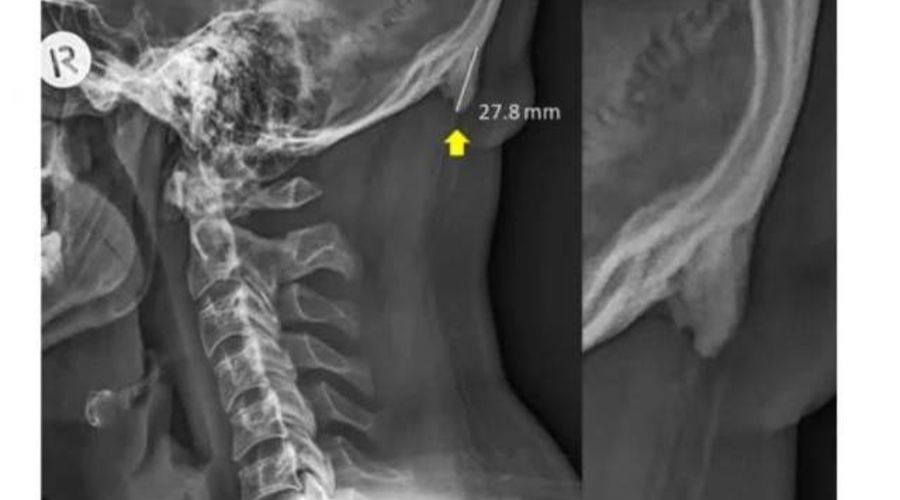

Австралийские ученые установили, что смартфоны провоцируют рост определенных костей черепа - роговидных шипов, представляющих собой костные наросты на задней части черепа. Они начинают образовываться из-за слишком частых наклонов головы.

Пользователи смартфонов чаще всего непроизвольно наклоняют голову вперед, поближе к экрану. Вес тела переносится с позвоночника на мышцы задней части головы, в сухожилиях и связках начинает расти роговидный шип.

В норме его длина не должна превышать трех миллиметров. Ученые изучили рентгеновские снимки 1200 добровольцев и пришли к выводу, что почти у 41% людей в возрасте до 30 лет размер шипа составляет от десяти до 31 миллиметра. Чаще всего "рога" встречались у мужчин.

Раньше такие наросты находили у пожилых людей, которые большую часть жизни занимались тяжелой физической работой. Пациенты испытывали хронические головные боли и неприятные ощущения в шее. Роговидные шипы у добровольцев не доставляли им дискомфорта. Их возникновение ученые связали с возросшей нагрузкой на мышцы шейно-черепного отдела из-за использования смартфонов, а не с генетической болезнью или последствиями перенесенных травм.